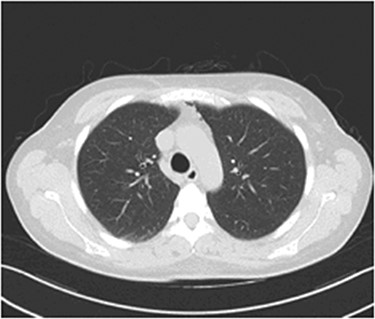

Our patient was put under oxygen therapy (Venturi 50%). As a precaution, antibiotic therapy was administered (teicoplanin/metronidazole), in order to prevent mediastinitis. During the second postoperative day, the clinical presentation of our patient was improved. The following day, the Venturi mask was replaced with a nasal cannula. In the fourth postoperative day, a computed tomography (CT) of the thorax was performed (Fig. 2), which showed a reduction of the amount of the air in the mediastinum, in concordance with the improvement of the clinical presentation of the patient. During the last day of hospitalization, the patient had no respiratory pathology symptoms, her clinical presentation was even more improved and she was discharged from the hospital on postoperative day 5.

Thorax CT during the fourth postoperative day: a significant reduction of the mediastinal gas collection is observed.